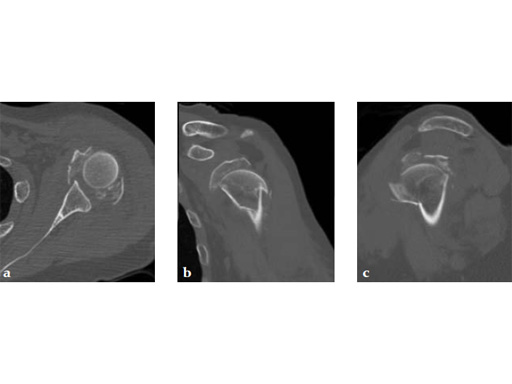

A 72-year-old woman suffered a four-part fracture of the left proximal humerus following a fall from a standing height. The patient underwent open reduction and internal fixation of the proximal humeral fracture.